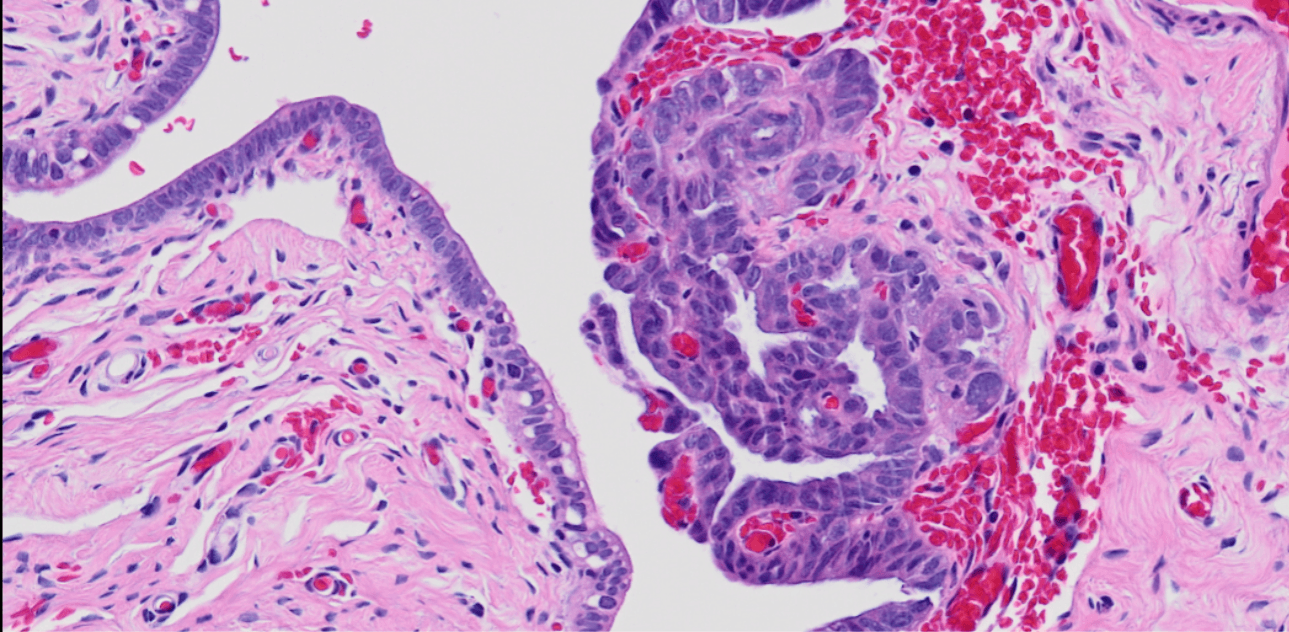

The team is identifying the early changes that occur in the fallopian tubes preceding ovarian cancer to establish strategies for identification of patients at high risk of developing ovarian cancer and for prevention of disease progression.

Collaborating institutions: UCL, University of Manchester, Stanford University (prior partner), OHSU, University of Cambridge